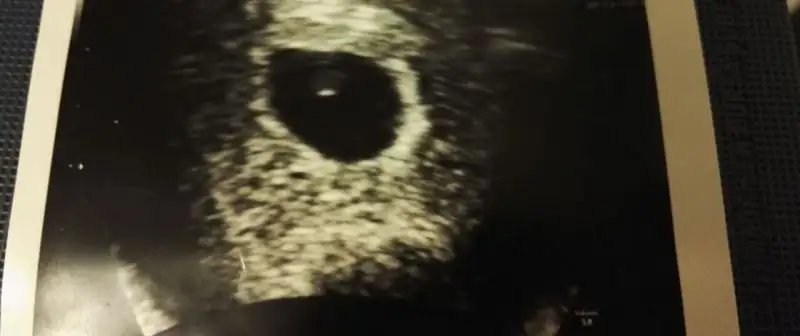

Çok sevimli bu Susam tanesi maşallah :)